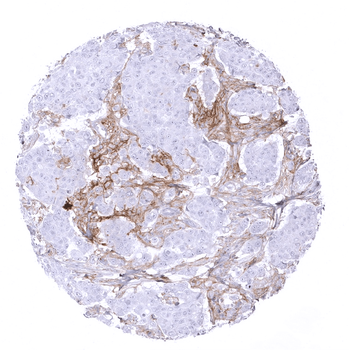

Breast Breast cancer NST with PD L1 negative tumor cells but intense PD L1 staining in tumor associated inflammatory cells.